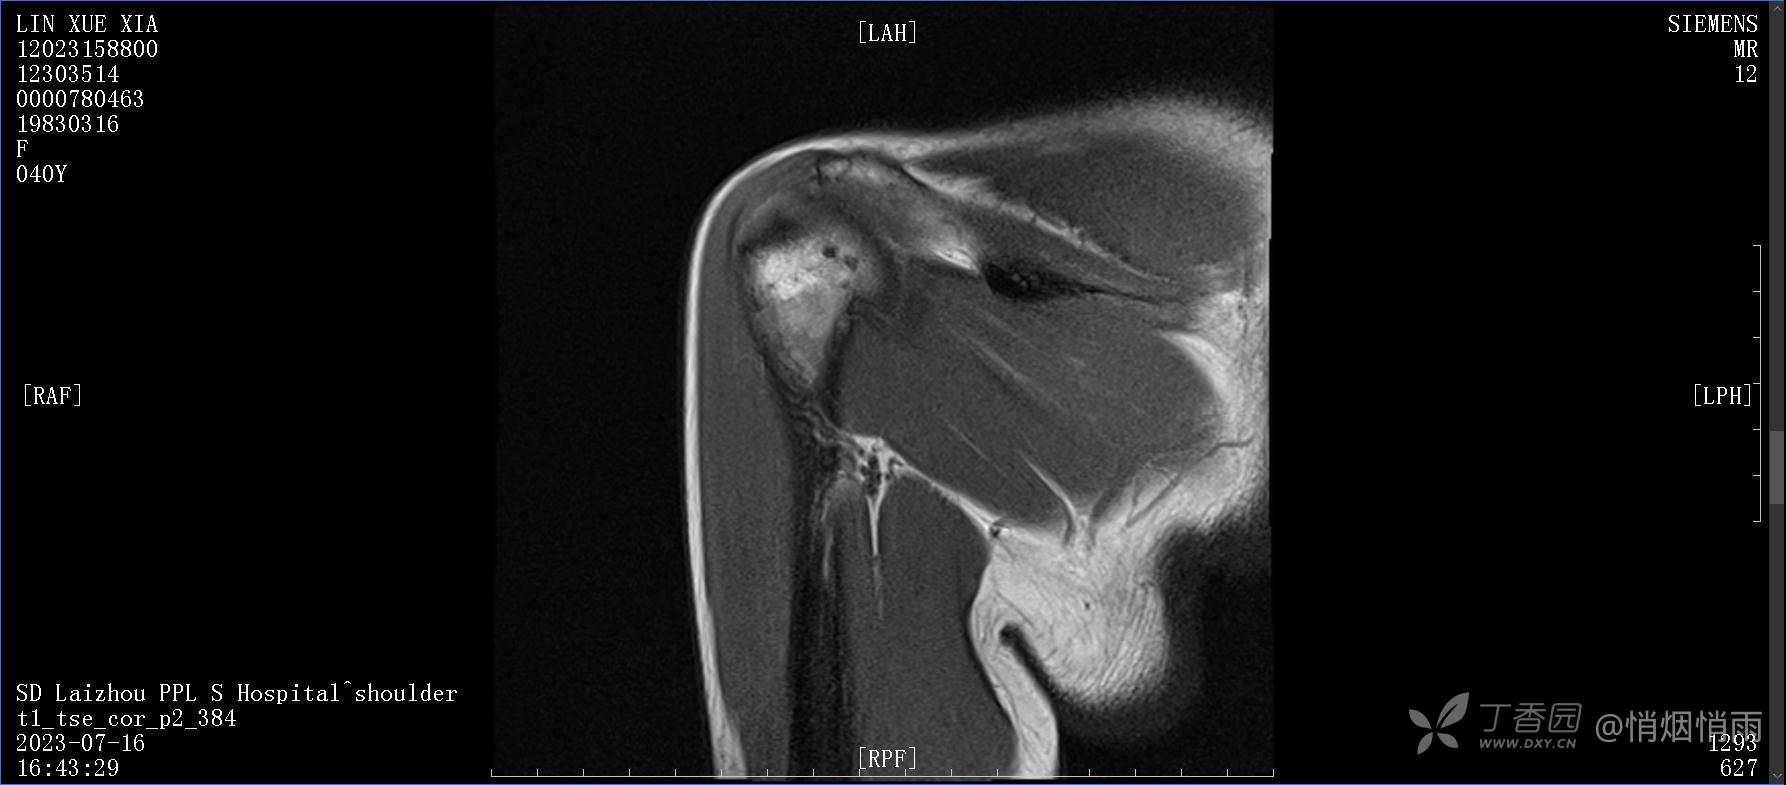

查体:右肩关节局部轻度肿胀,肩胛区压痛明显,痛处不固定,肩关节痛性活动受限,jobe test(+),lift -off test(+),中指、环指感觉较余指减退,余肢端感觉及血运情况可。

目前的诊断,暂时依据辅助检查诊为肩袖损伤,但是患者疼痛的性质和特点,却不是单纯的肩袖损伤所致。考虑过胸廓出口综合征,但是该疾病会出现肩胛区的疼痛吗?(由于考虑到费用的问题,没再进行下一步的检查)带状疱疹会有如此的症状吗?